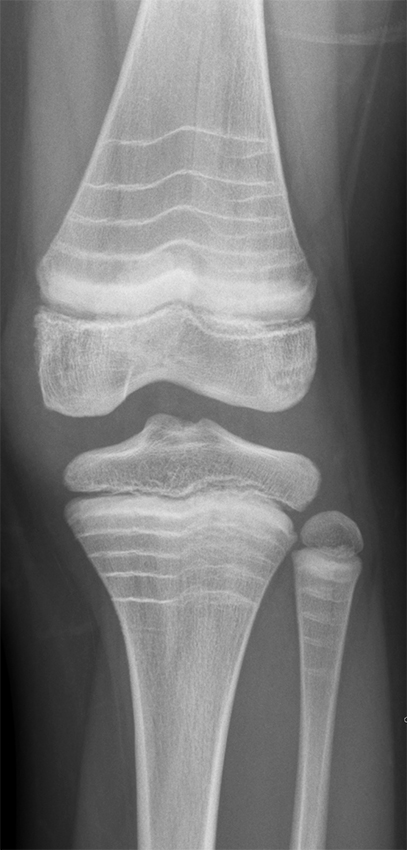

Røntgenbiletet viser eit kne med multiple, tverrgåande, sklerotiske (kvite) linjer i metafysen både i femur og tibia hos ein gut i tenåra. Pasienten har også tilsvarande funn i fleire andre ledd. Han har diagnosen osteogenesis imperfecta type 1 og har i fem år fått intravenøs behandling med zoledronsyre (bisfosfonat). Kvar av dei tverrgåande linjene svarer til ein behandlingsrunde/injeksjon med bisfosfonat. Hyppigare injeksjonar gjev kortare avstand mellom linjene. Linjene er vanlegast i metafysane, men kan også finnast i epi- og apofysane. Desse sklerotiske linjene er resultat av auka beinmineralisering (1) og er ein indirekte respons på hemming av osteoklastaktivitet som følge av behandlinga. I 2007 kom eit forslag om å nemne desse forandringane for sebralinjer (zebra lines) (2).

Medikamentell behandling med intravenøs bisfosfonat vert vurdert ut frå brothistorikk og alvorsgrad. Bisfosfonatbehandling aukar mineraliseringa av beinvevet, men påverkar ikkje sjølve kollagenfeilen. Zoledronsyre vert gitt kvar sjette månad frå toårsalderen og vanlegvis fram til barnet er ferdig med å vekse, men behandlingslengda vert vurdert individuelt. Zoledronsyre er ikkje godkjent til bruk under to års alder, så før det nyttar ein difor månadlege infusjonar med pamidronat.